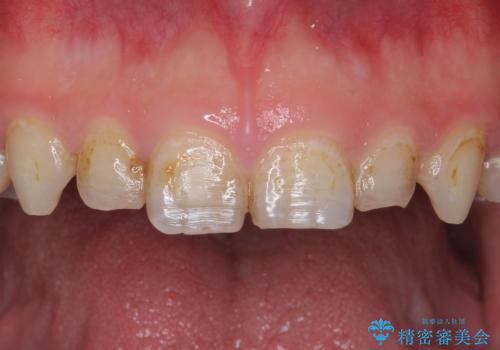

- K-POP(Kポップ)アイドルのような歯にしたいと希望され来院された患者様です。

矯正を途中でやめてしまったとのことで、歯に矯正の接着材が残っており着色も顕著でした。

奥歯の咬合面にはレジンが盛られた状態でした。